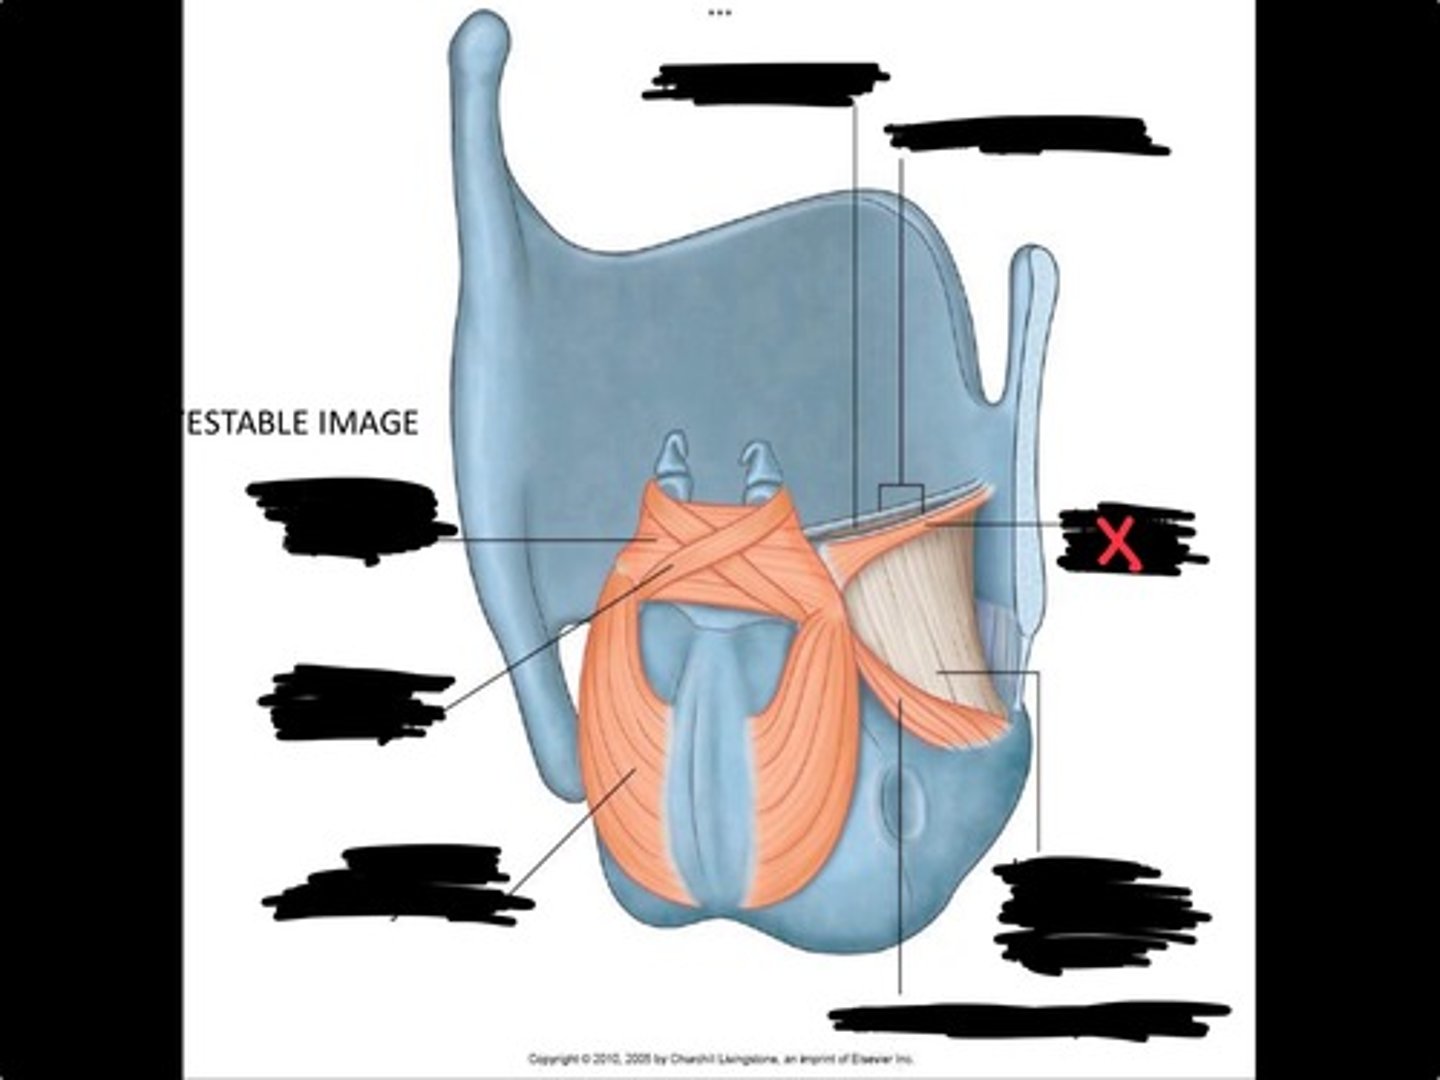

Vocal process of arytenoid

Conus elasticus

Vestibular ligament

Quadrangular membrane

Epiglottis

vocal ligament

Aryepiglottic ligament

Muscular process of arytenoid

Corniculate cartilage

Posterior crico arytenoid

oblique arytenoid

transverse artyenoid

Rima glottidis

Vocal ligament

Vocalis muscle

Lateral cricothyroid ligament

Lateral cricoartenoid